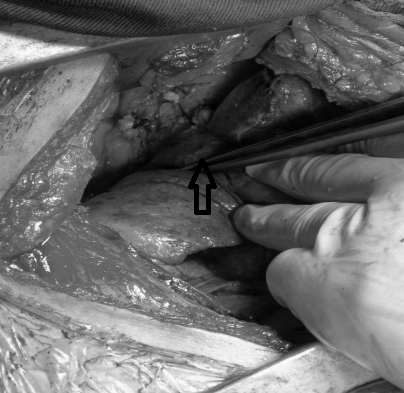

由于手术难度大,术中不可预知情况多,经过术前讨论高兴才主任认为,患者右主支气管狭窄长度约1-2cm,可实施“支气管成形术”,虽然有术中切除肺叶的可能,但患者比较年轻,应尽最大可能保留右肺上叶。经过积极术前心肺功能准备后,于7月16日,高兴才主任医师、冯光强副主任医师在麻醉科胡强夫主任及其团队的配合下,全麻双腔插管给霍先生实施了“右主支气管成形术”。打开胸腔后发现,胸腔广泛粘连,而且因为炎症的原因,患者组织脆、水肿,解剖发育异常,都给手术增加了难度。但是,为了保留患者右上肺,术者仔细操作,认真分离,终于完整切除了狭窄的气管,同时成功吻合断端,术中患者顺利脱机后返回病房。

▲ 箭头所示切开后狭窄气管